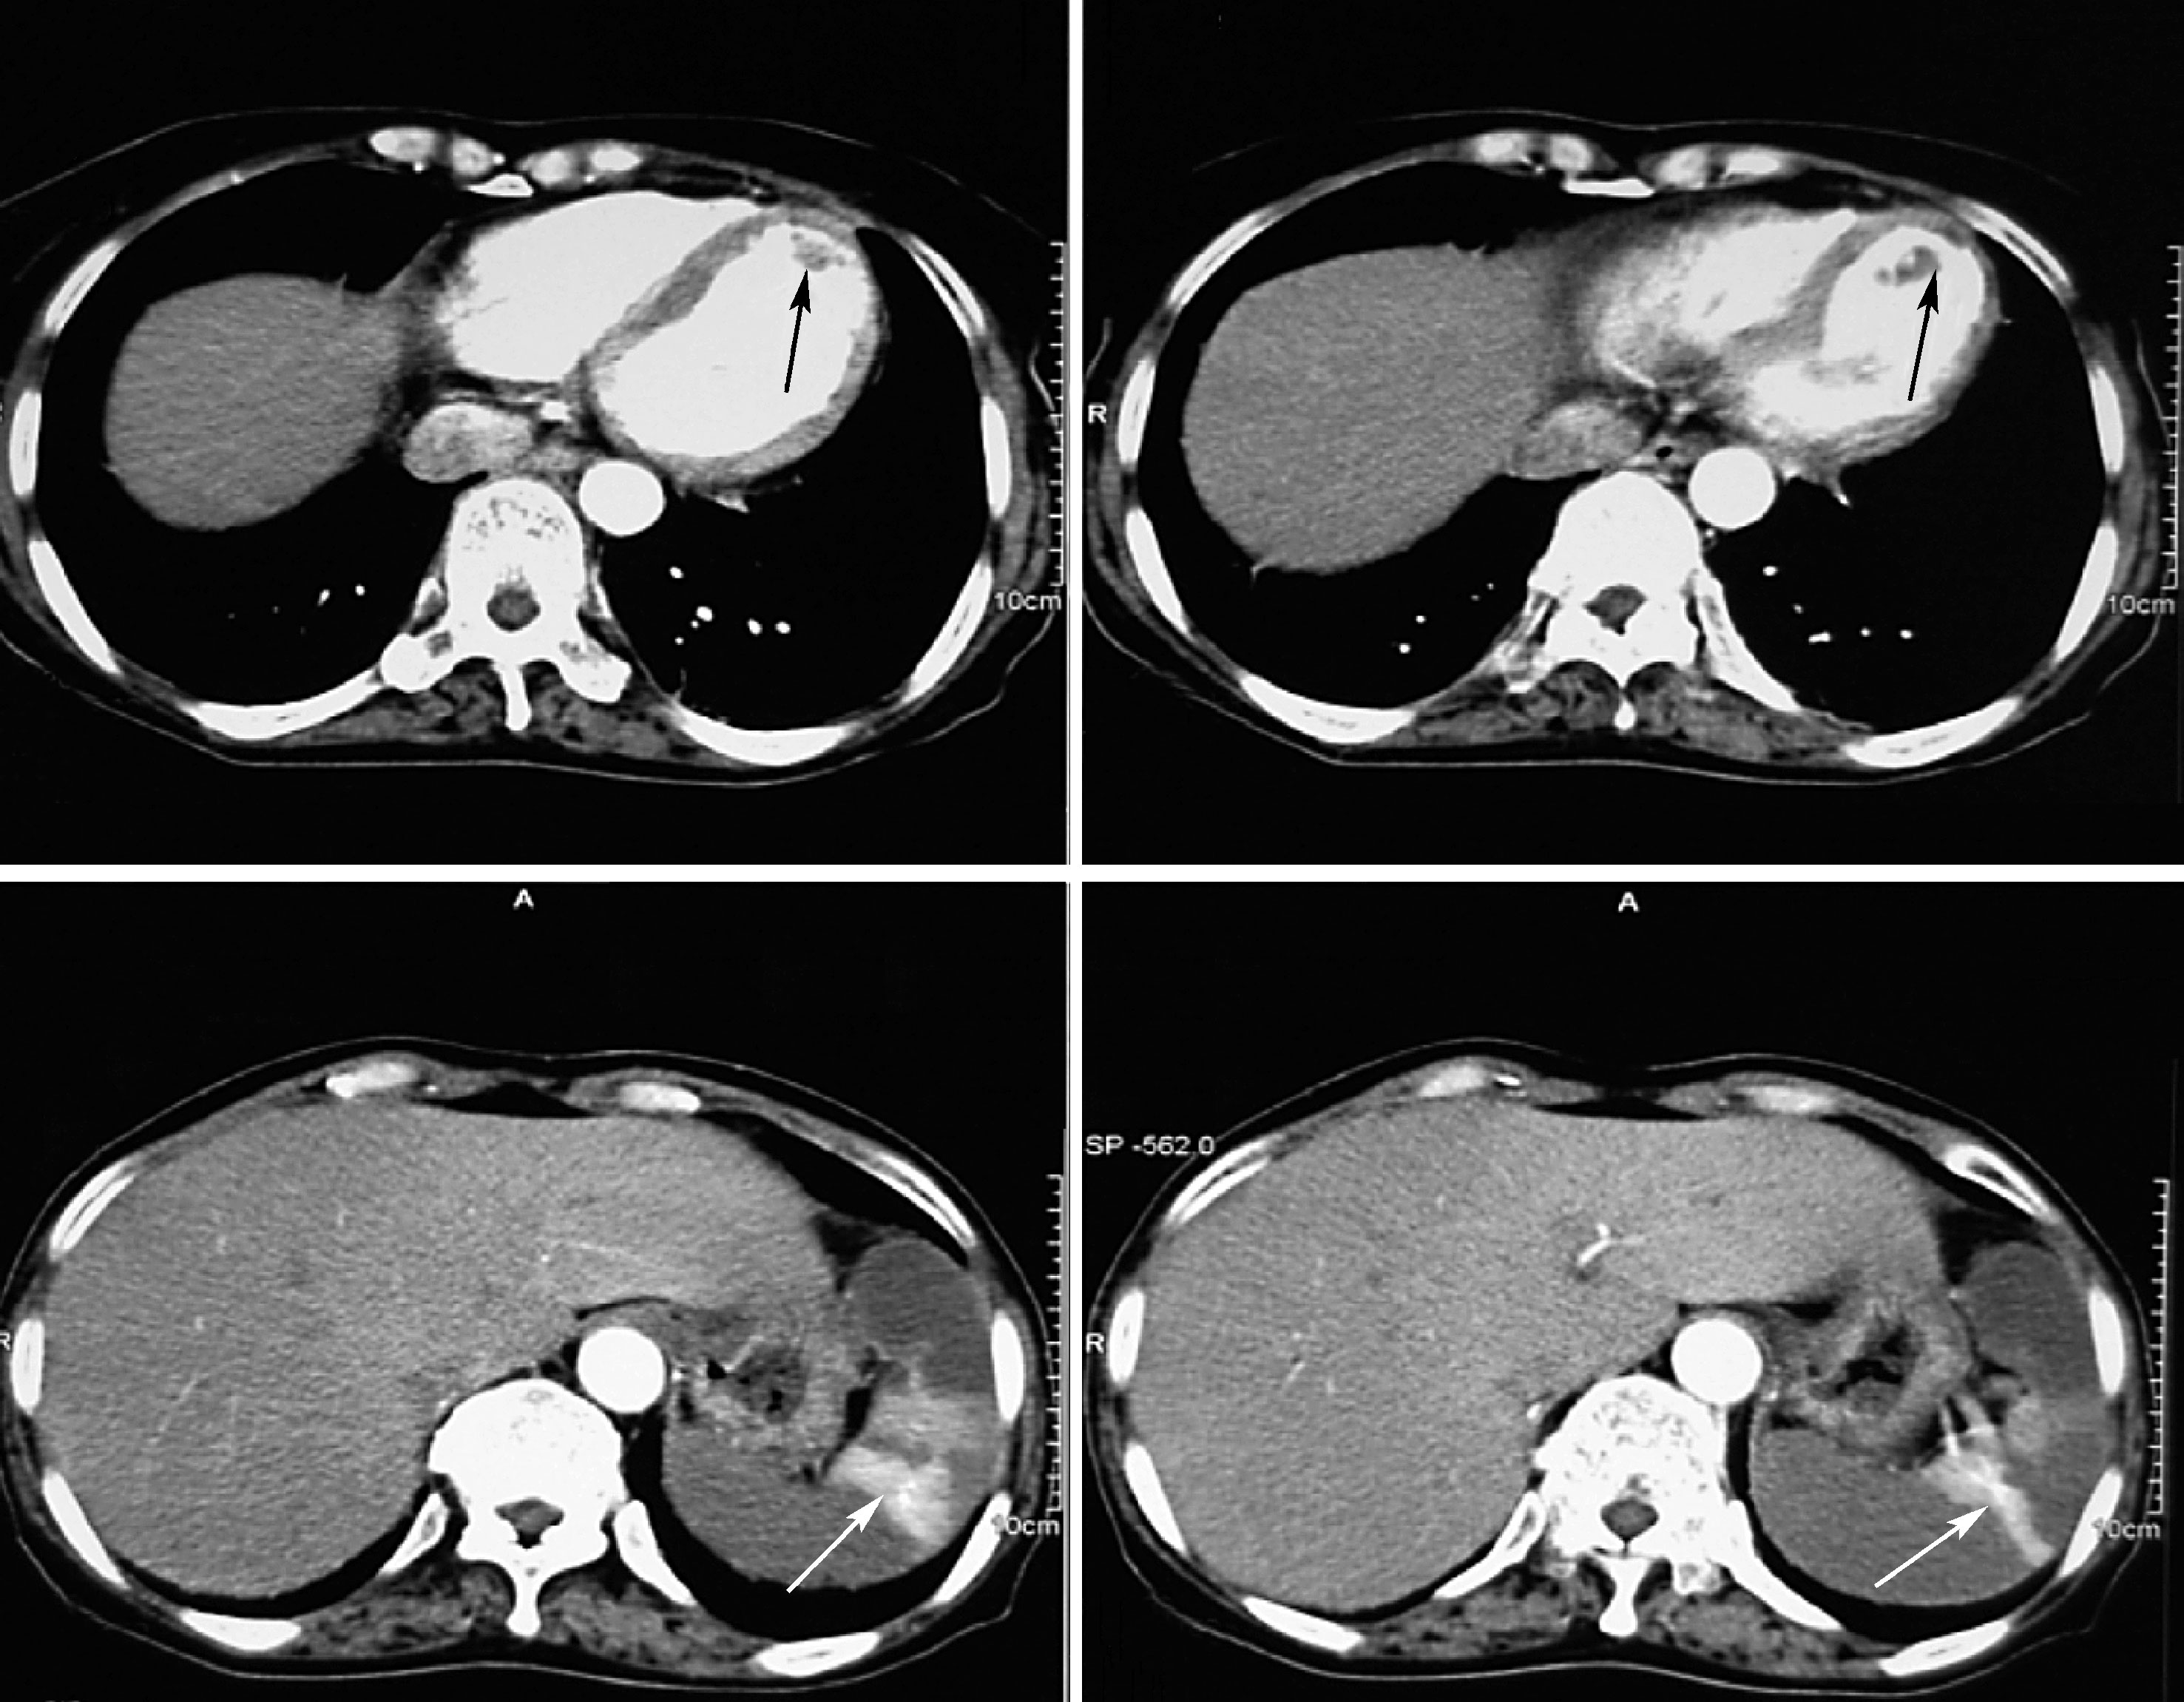

住院第16日进食后突然出现上腹部疼痛,呈钝痛,无肩背部放射痛,无恶心、呕吐、腹泻、呕血及黑便。查体:左上腹压痛、反跳痛,无肌紧张。急诊超声及CT示脾梗死、胆囊炎、腹膜后多发淋巴结肿大、左心室近心尖部血栓(图10-2、图10-3)。明确诊断为左心室血栓、急性左心功能不全、阵发性房扑、急性脾梗死。给予低分子肝素4250IU皮下注射每12小时1次,华法林2.5mg每天1次抗凝治疗3天后,INR由1.46升至2.81,停用低分子肝素。同时按需口服双氯芬酸钠止痛,继续利尿纠正心衰,抗结核、减弱抗感染力度(换为头孢他啶)治疗。

图10-2 上腹部增强CT

左心室血栓、脾梗死(箭头所示)

图10-3 心脏超声

A.左心室血栓(箭头所示);B.左心室血栓消失